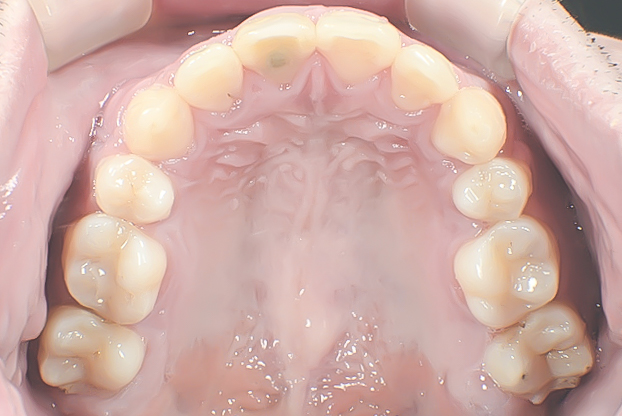

上顎の治療です。

前から4番目の歯(小臼歯)が抜去され、装置が装着されています。抜歯によって得られたスペースを使ってきれいなアーチ状に並べていきます。

叢生が改善し、アーチ状に並んでいます。

ガタガタがなくなり、きれいなアーチ状の上顎歯列です。